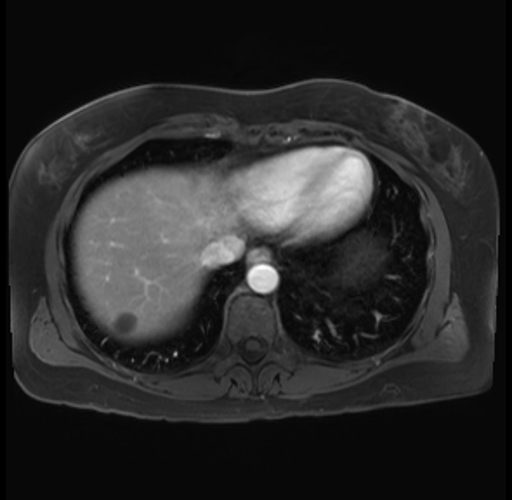

Imaging Analysis

Look through the patient's CT scan to identify any areas of concern for the necessary procedure.

Based on your CT findings, which issue(s) are present and would give reason for "planned slowing down moment(s)" in this case?